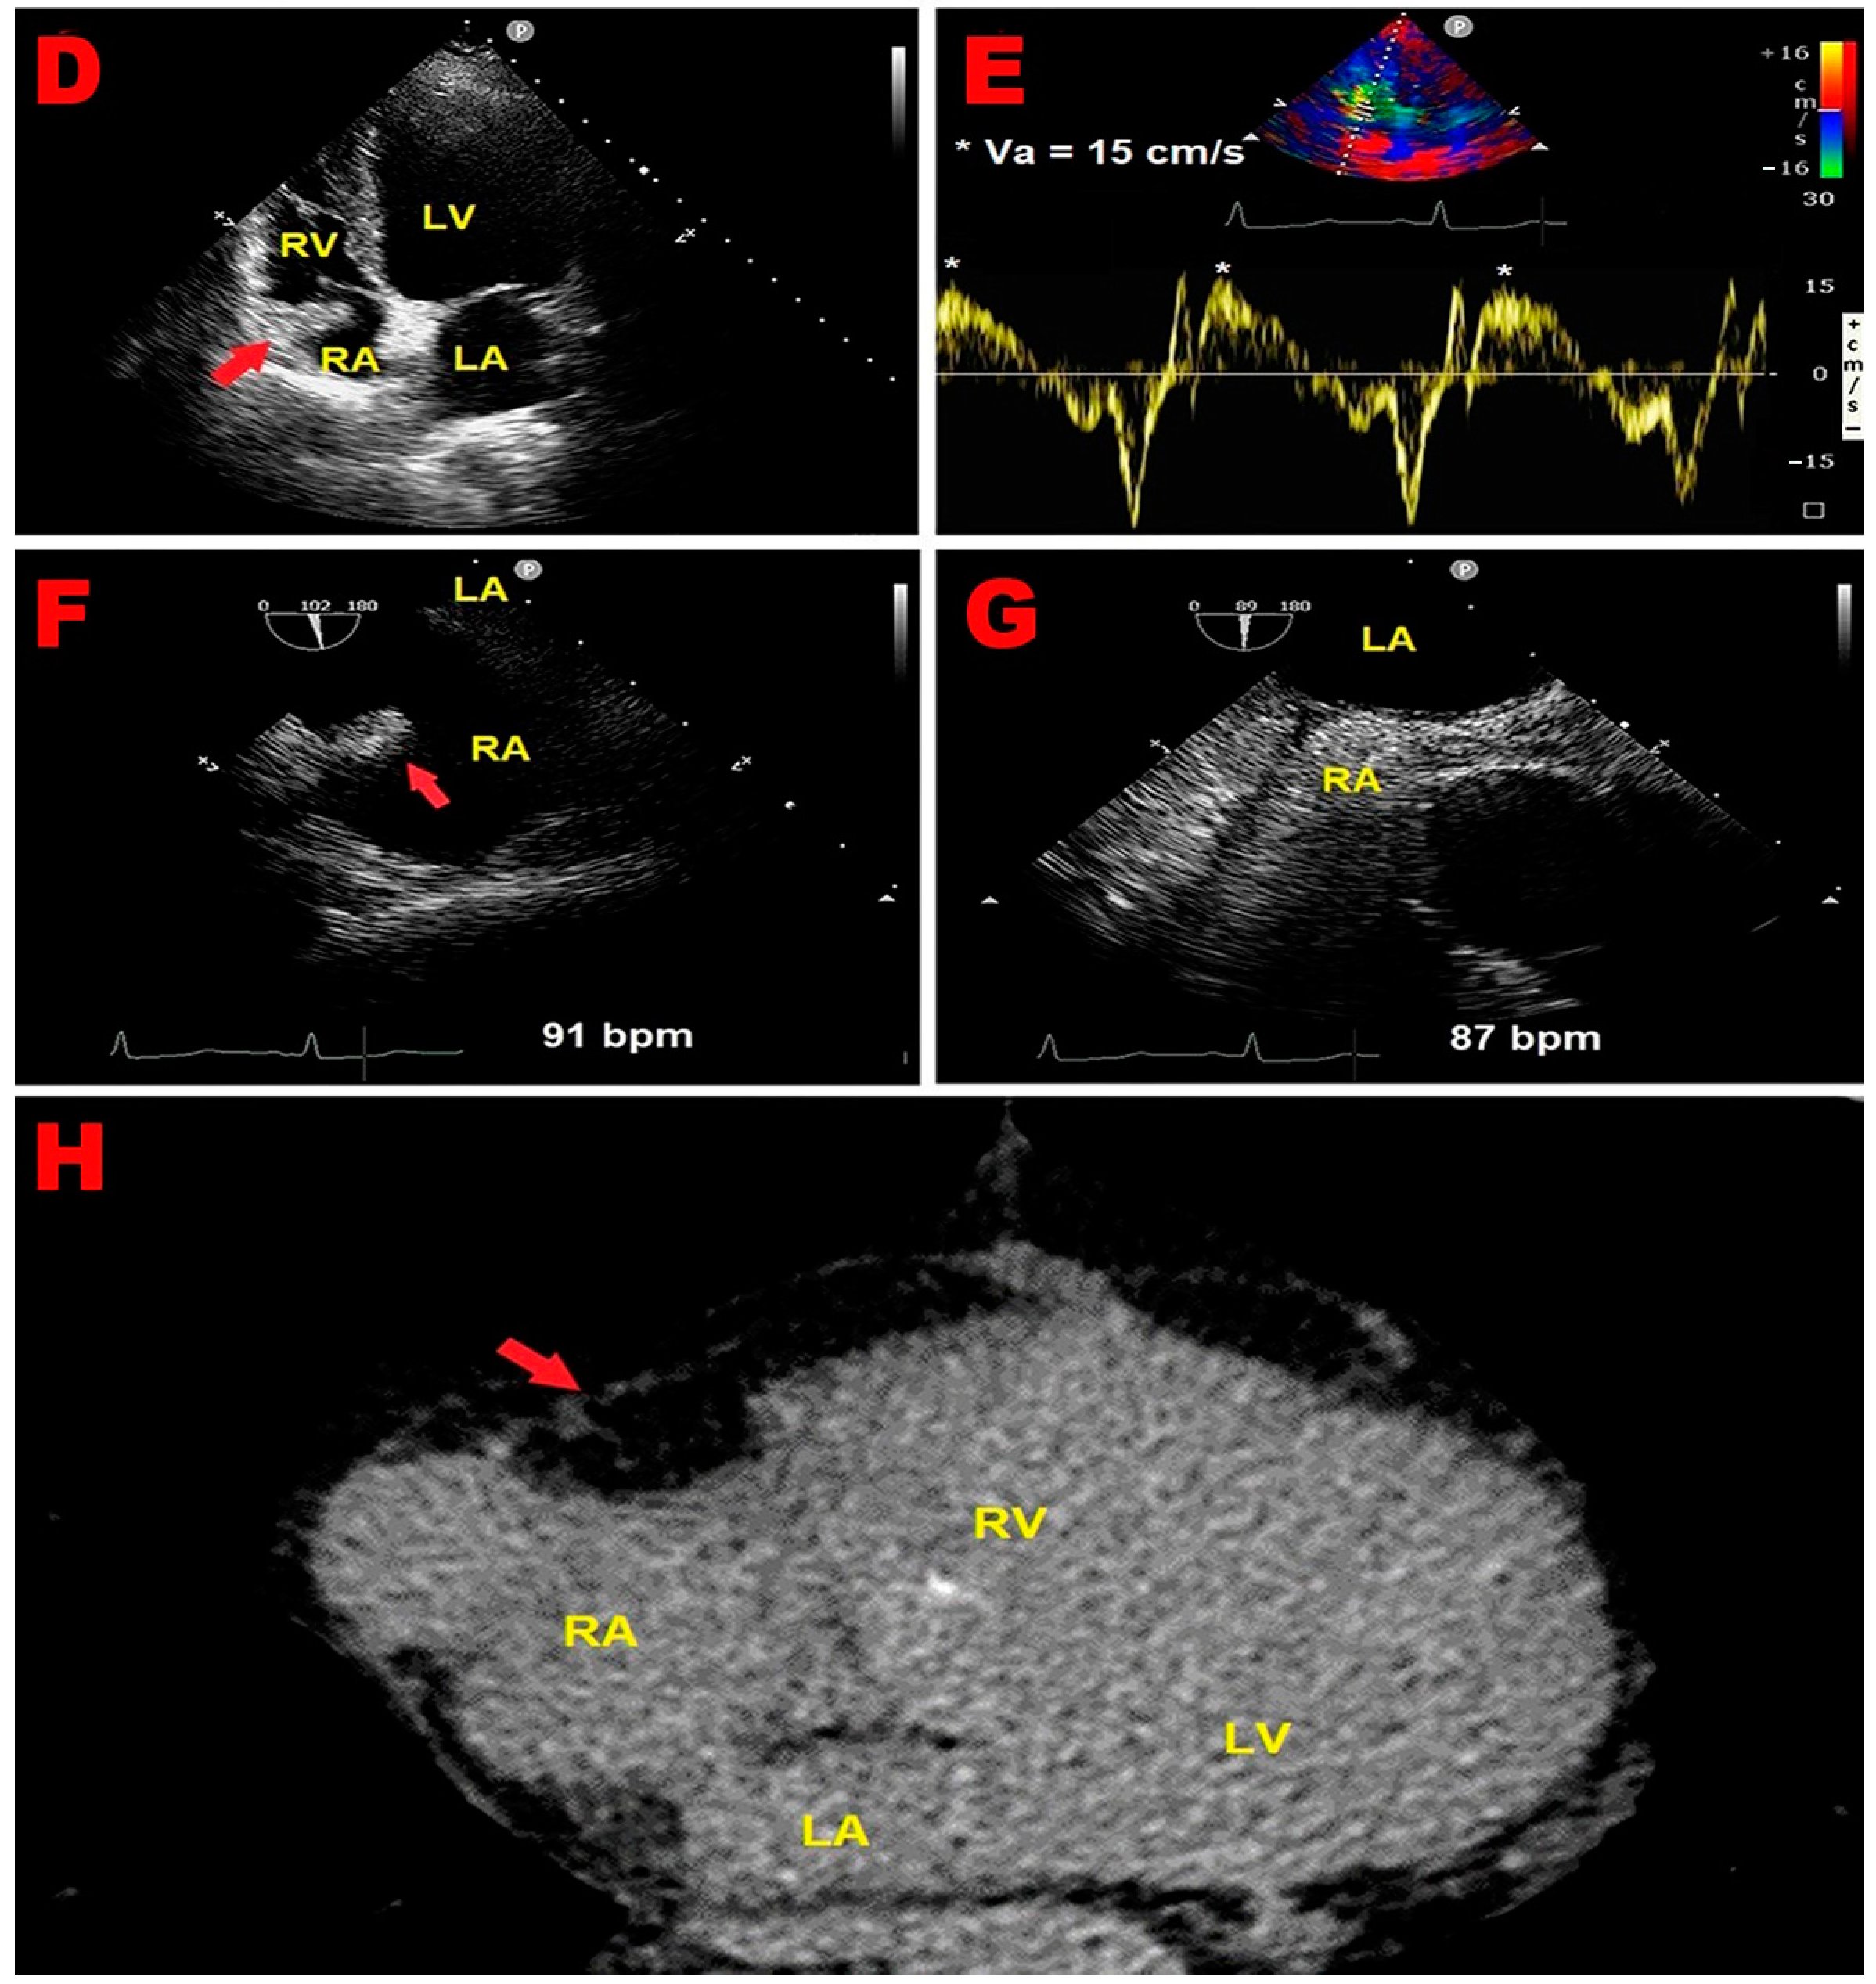

2.1. Clinical Case 1

2.2. Clinical Case 2